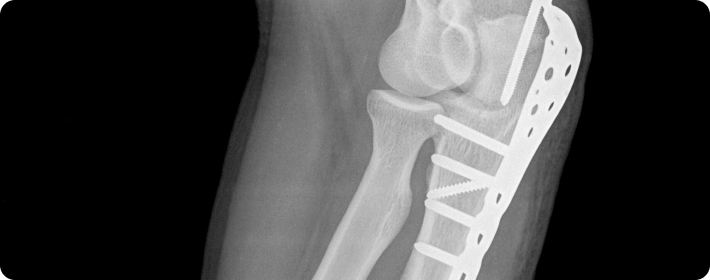

골절고정술

부러진 뼈를 정확한 위치에 맞춘 뒤, 금속판, 나사, 핀 봉 등을 이용해 단단히 고정하여 뼈가 바르게 치유되도록 돕는 수술입니다. 뼈의 정렬을 유지하고 회복을 촉진하는 데 중요한 치료입니다.